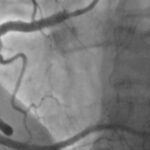

Jego specyfika polega na tym, iż lekarze użyli minimalnej ilości kontrastu w trakcie angioplastyki wieńcowej, czyli naprawy zwężeń w tętnicach wieńcowych u pacjenta cierpiącego na chorobę wieńcową.

Mateusz Wiśniowski, starszy asystent w Pracowni Radiologii Zabiegowej powiedział, iż procedury kardiologii inwazyjnej wymagają podania środka kontrastowego, co wiąże się ze zwiększonym ryzykiem uszkodzenia nerek, a jednym z rozwiązań, które pomaga ochronić nerki pacjenta jest wykonanie zabiegu techniką minimalnej objętości kontrastu, bądź nie używania środka kontrastowego w trakcie zabiegu.

– Zabiegi te wykonuje kilka ośrodków. Pomagają one ochronić pacjentów przed uszkodzeniem funkcji nerek – dodał lekarz.